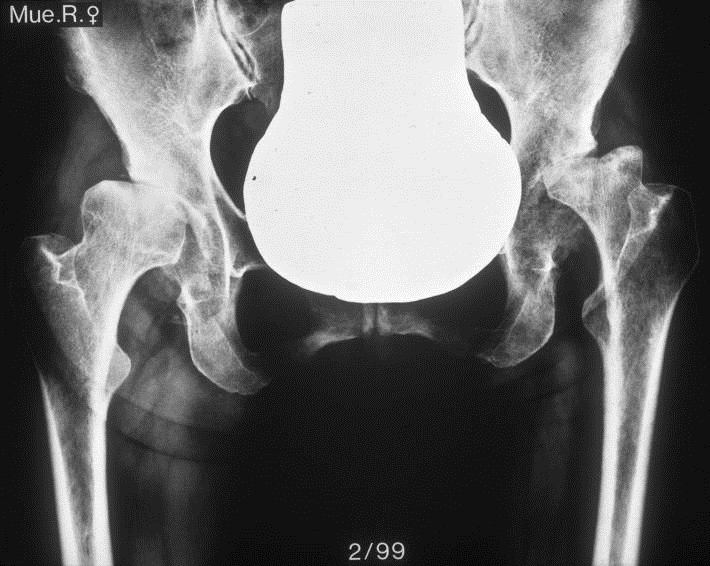

Fallbeispiel

Weiblich, 55 Jahre. Es zeigt sich eine schwere Dysplasiearthrose der

rechten Hüfte (links im Bild) sowie eine Subluxation des linken Hüftkopfes mit

partiellem Kopfeinbruch.